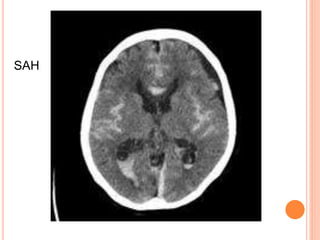

CT SCAN

 Mandatory initial investigation

 Haemorrhage appears instantly as a hyperdense

area

 Infarct appears as a hypodense area

 Infarct may not appear before 48 hrs

 MRI may be done instead but ct scan is more

sensitive for detecting haemorrhage

 Diffusion weighted MRI is good for identifying

ischaemic lesion.

SAH